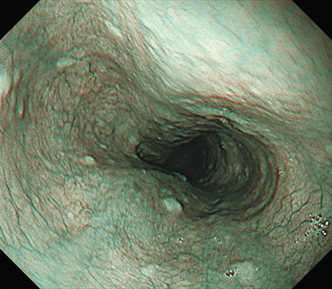

EVIS LUCERA ELITE × GIF-1200N 、EVIS X1 × GIF-H190N 什器比較画像

面順次式、同時式で色味の違いはありますが、どちらもハイビジョン画質にて観察可能です。

EVIS LUCERA ELITE×GIF-1200N